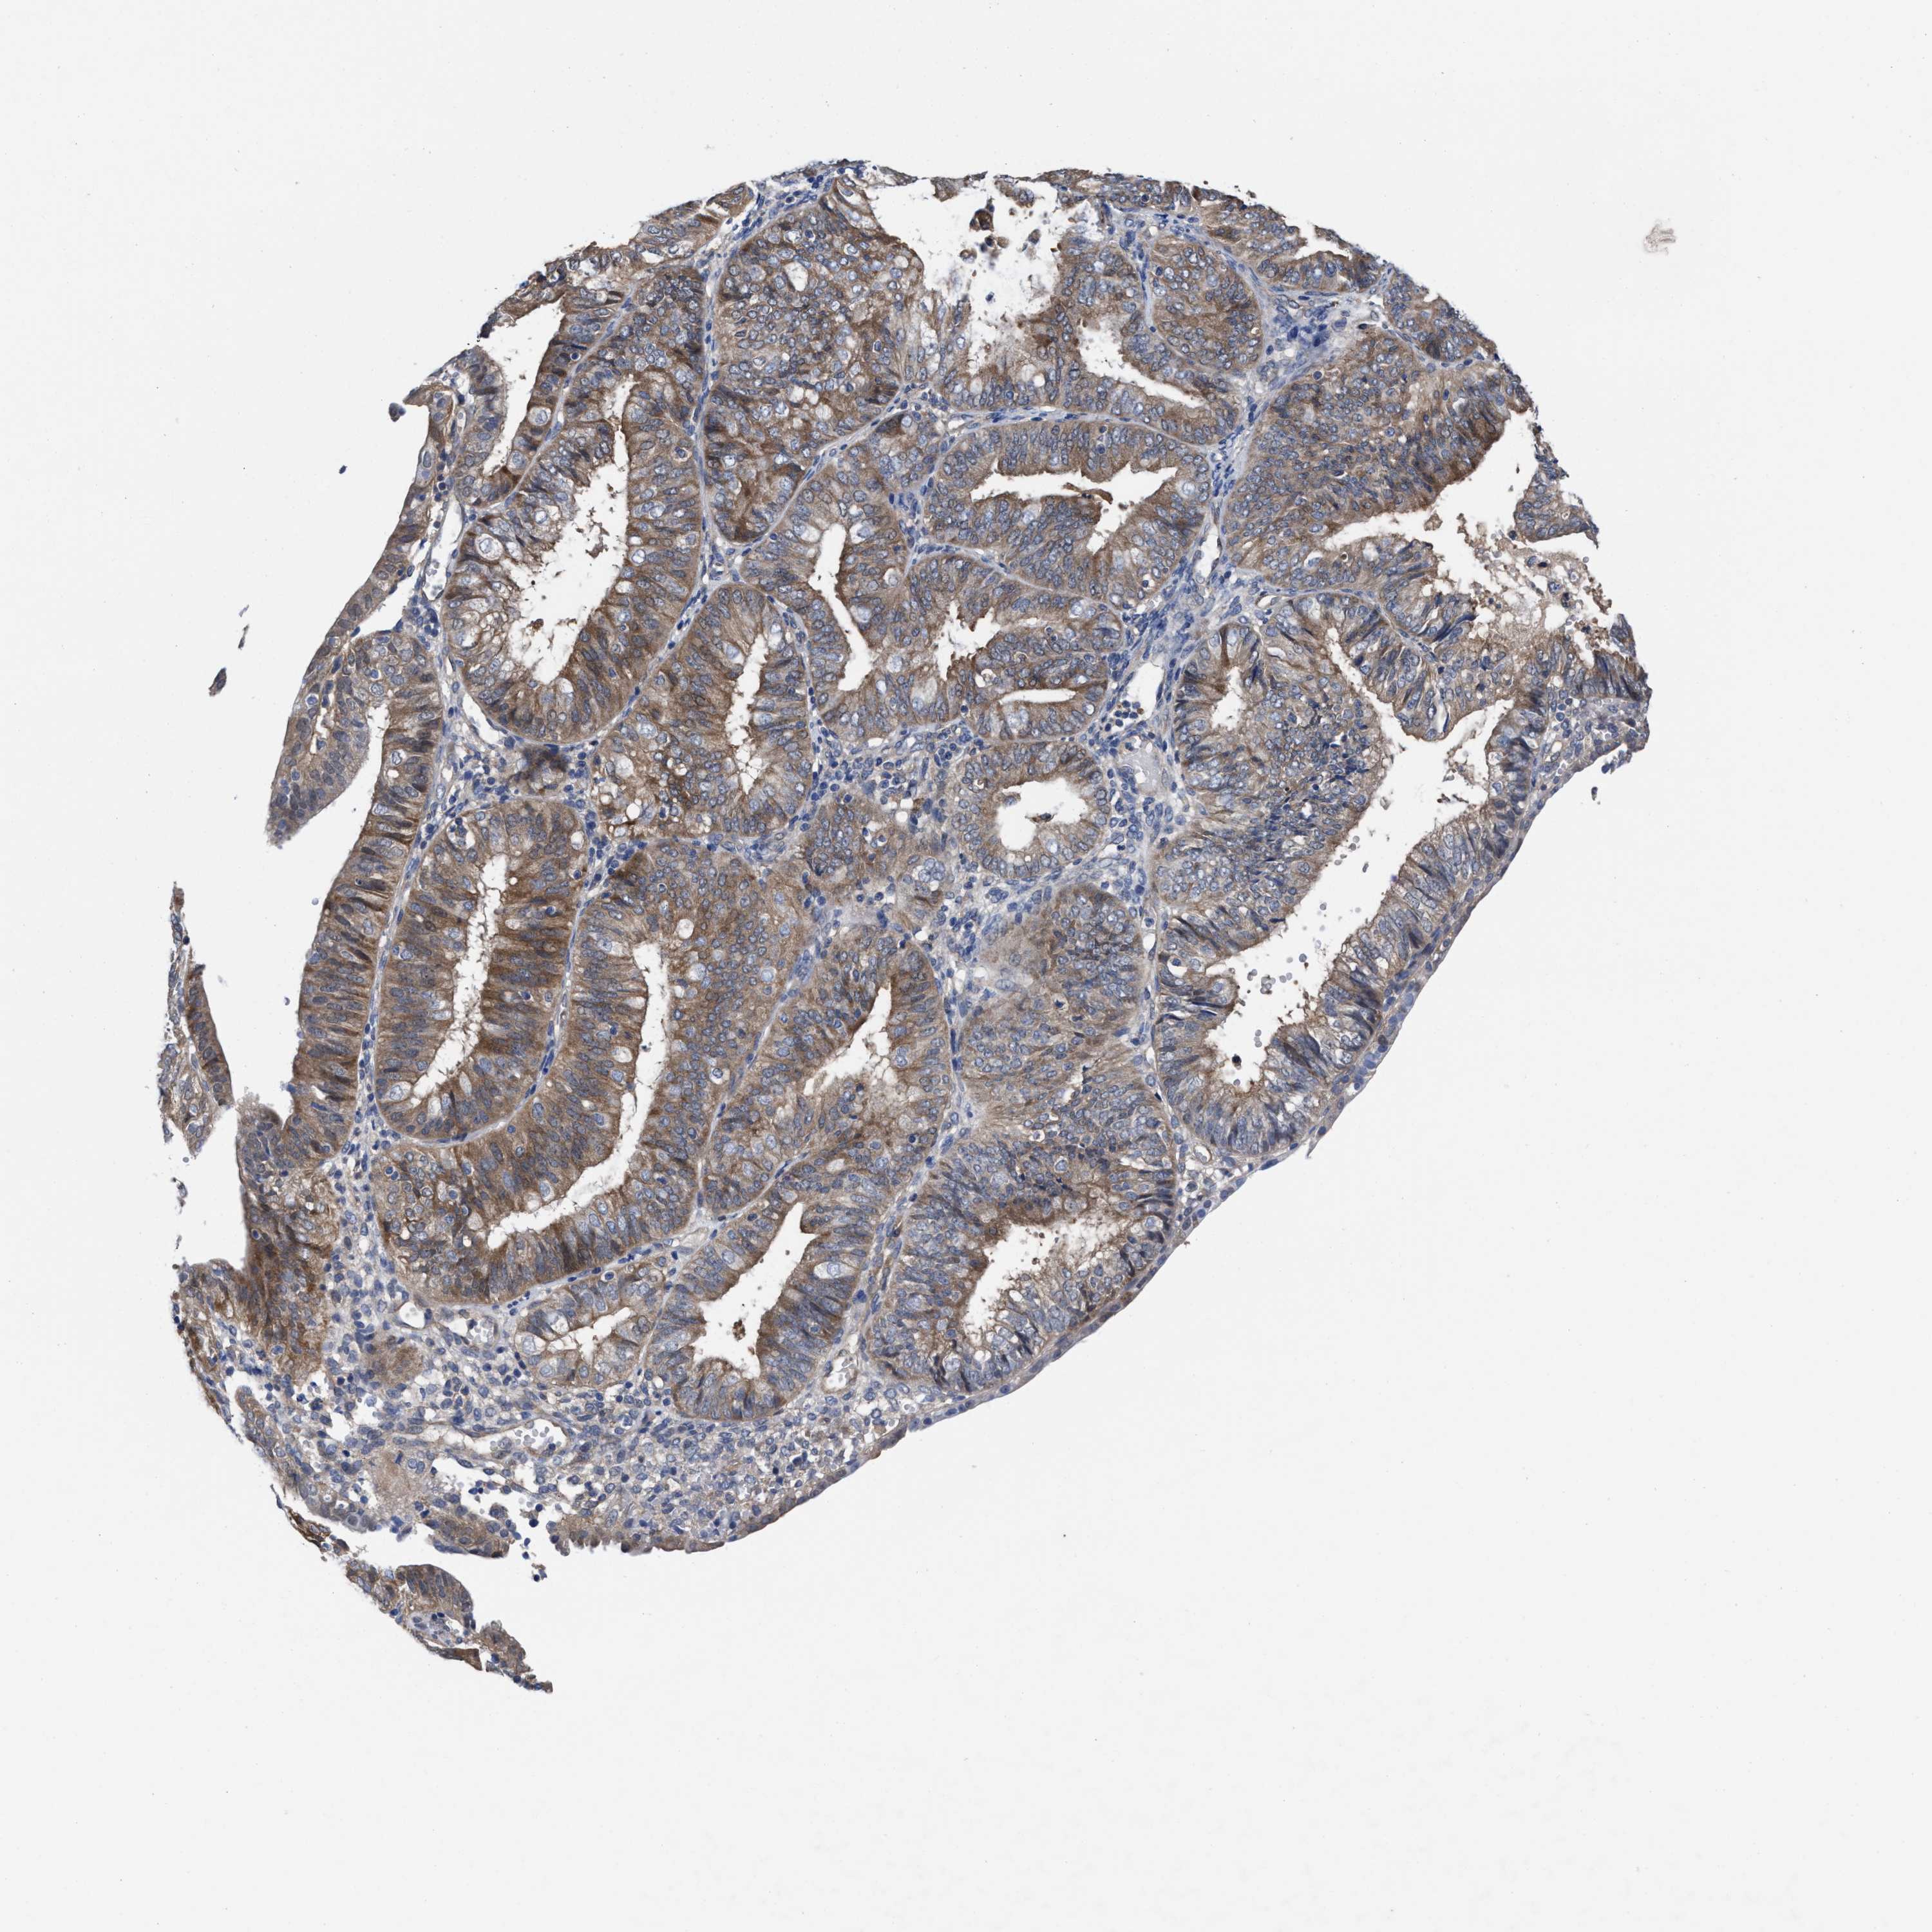

ENDOMETRIAL CANCER - Protein expressioni

A mouse-over function shows sample information and annotation data. Click on an image to view it in a full screen mode. Samples can be filtered based on level of antibody staining by selecting one or several of the following categories: high, medium, low and not detected. The assay and annotation is described here.

Note that samples used for immunohistochemistry by the Human Protein Atlas do not correspond to samples in the TCGA dataset.

Antibody stainingi

Antibody staining in the annotated cell types in the current human tissue is reported as not detected, low, medium, or high, based on conventional immunohistochemistry profiling in selected tissues. This score is based on the combination of the staining intensity and fraction of stained cells.

Each image is clickable and will lead to virtual microscopy that enables deeper exploration of all samples and also displays staining intensity scores, fraction scores and subcellular localization as well as patient and tissue information for each sample.

Antibody HPA022931

Staining

High

Medium

Low

Not detected

Intensity

Strong

Moderate

Weak

Negative

Quantity

>75%

75%-25%

<25%

None

Location

Nuclear

Cytoplasmic/membranous

Cytoplasmic/membranous,nuclear

Adenocarcinoma, NOS

Adenoma, NOS